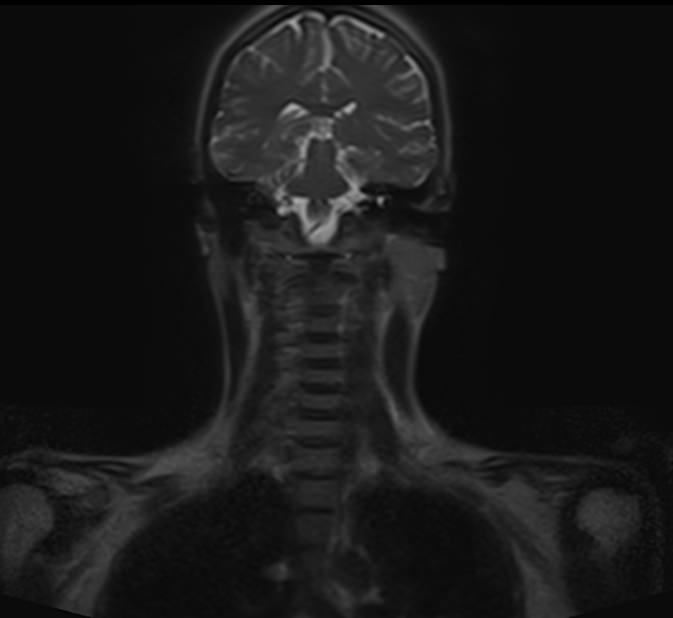

Скрининговое обследование всего тела с помощью метода магнитно-резонансной томографии включает в себя сканирование головы, шеи и туловища с органами брюшной полости, забрюшинного пространства и малого таза.

В нашей клинике МР-скрининг всего тела проводится на новейшем высокопольном томографе экспертного класса TOSHIBA VANTAGE TITAN 1,5 Тесла. Аппарат послойно сканирует структуры всего тела в различных плоскостях в виде тончайших срезов с шагом от 1 мм, затем посредством инновационных компьютерных программ преобразует полученные данные в трехмерные изображения превосходного качества.

• всех структур головного мозга;

• мягких тканей области шеи;

• позвоночника и спинного мозга;